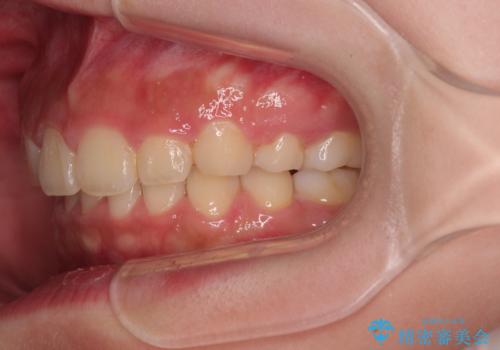

- 飛び出した上顎前歯と、閉じにくい唇、口元の突出した印象の横顔を気にして来院された患者様です。

骨格的な上顎前突であり、上下前歯の前後的な距離が大きいため、上顎は左右第一小臼歯を、下顎は左右第二小臼歯をそれぞれ2本抜歯することで前歯が接触するようにし、さらには奥歯の咬み合わせも、より理想的な状態へ近づけていくこととしました。

3年以上はかかる難症例であるため、表側のワイヤー装置にて治療を行うこととしました。

事前の予想通り、長期間を要する治療となりましたが、横顔の印象が劇的に変化し、患者様には大変満足していただきました。